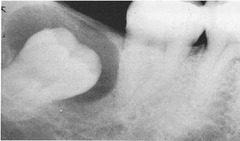

Mulberry Molars (see image)

irregularly shaped molars with poorly defined cusps also caused by syphilis

Mulberry Molars